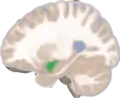

Left lateral view of the amygdala in an average human brain

Amygdala highlighted in green on sagittal T1 MRI images